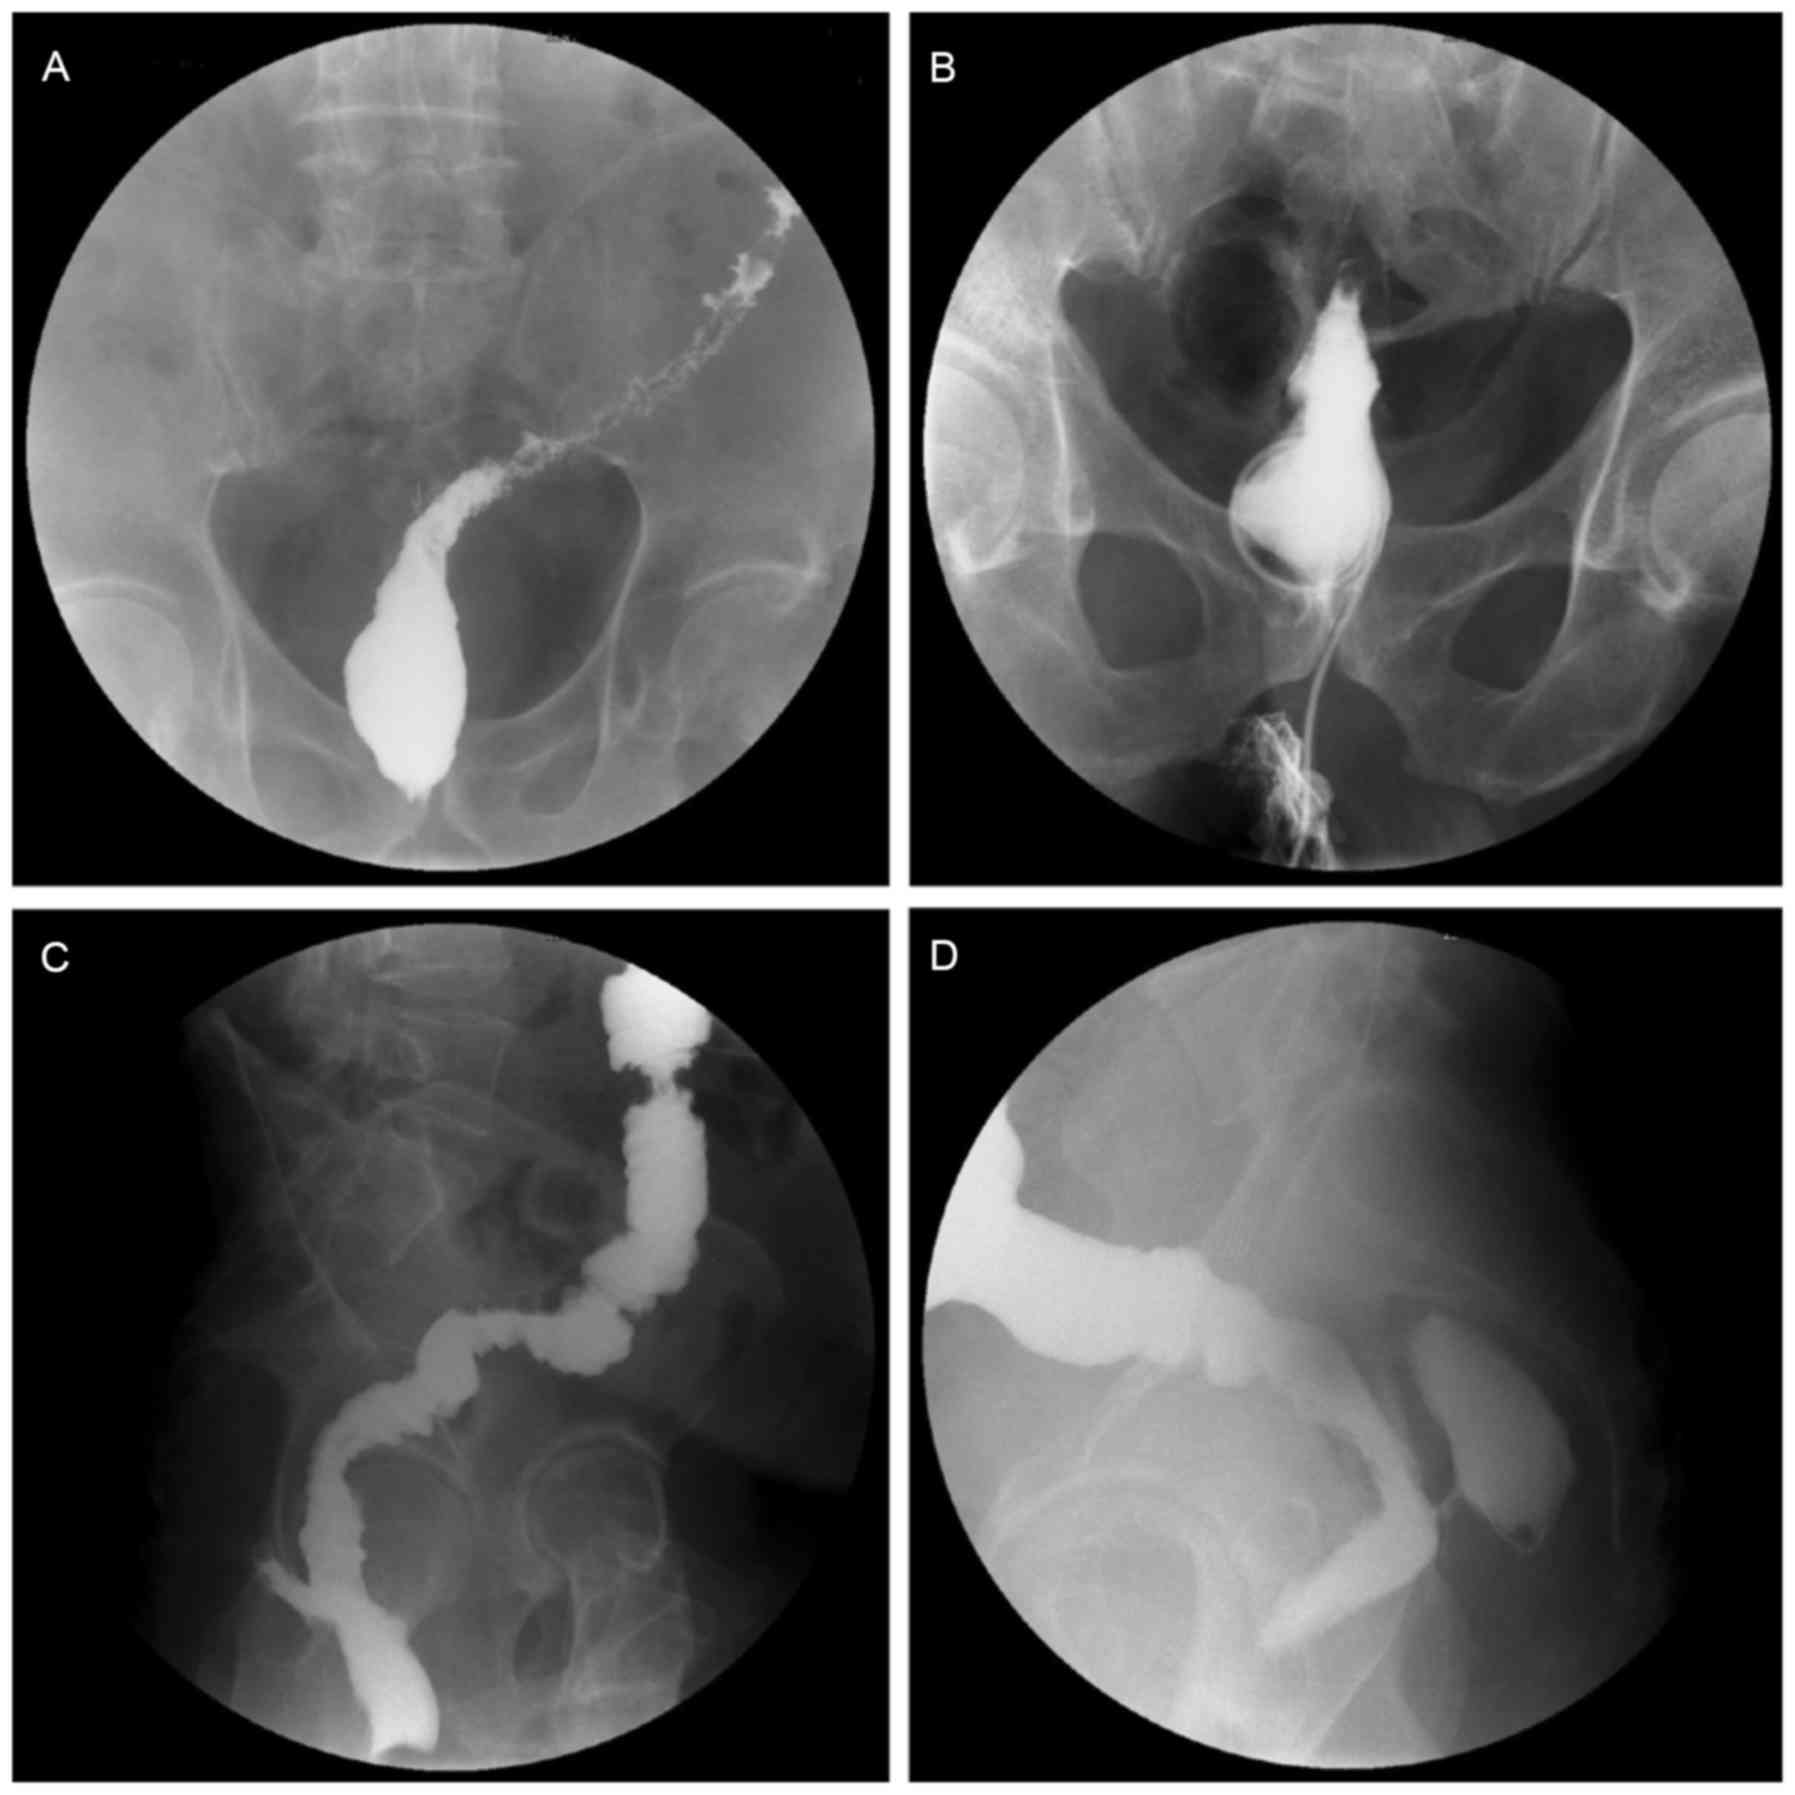

Routine examination of the anastomosis was performed at ~7 and 14 days postoperatively by digital rectal examination. If necessary, a Urografin enema colonography was performed to assess the anastomosis. Digital rectal examination and colonography were conducted on all patients in the ileostomy group prior to the reversal surgery in order to avoid AL, dehiscence and stenosis (Fig. 3).

Figure 3.

Colonography for assessing anastomosis (X-ray film image): (A) Normal anastomosis, (B) anastomotic stenosis (posteroanterior view), (C) anastomotic leak (oblique view) and (D) anastomotic leak (lateral view).

AL was defined as a defect in intestinal wall integrity at the colorectal or coloanal anastomosis site, leading to communication between the intra- and extra-luminal compartments, and may be diagnosed through digital rectal examination or colonography. Anastomotic dehiscence was defined as incomplete anastomosis, usually detected through digital rectal examination and lacking clinical manifestations. Anastomotic stenosis was detected upon digital rectal examination or colonography, and an additional procedure to relieve the stenosis was inevitably required prior to undertaking the reversal surgery.